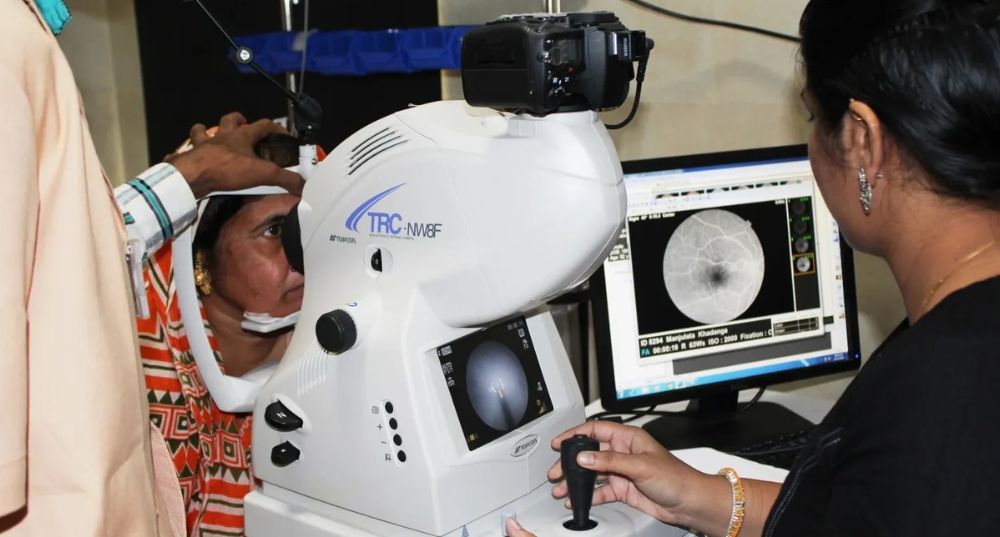

Innowave Healthcare is a leading Indian MedTech software company revolutionizing diagnostic imaging since 2013. We offer AI-powered PACS-RIS, teleradiology, tele-ophthalmology, and workflow solutions trusted by diagnostic centers and hospitals across India, Southeast Asia, West Asia, Africa, and North America. Our flagship Freedom Nano platform is a cost-effective, multi-specialty workflow system supporting radiology, cardiology, ophthalmology, and more. We empower clinicians with fast, accurate, and connected diagnostics—even in remote locations. At Innowave, we innovate to make healthcare smarter, more accessible, and truly transformative.